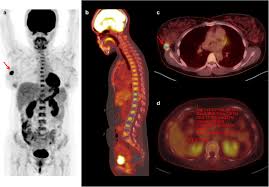

여기에 방사성 핵종 F-18를 붙여(F-18 FDG라고 함) 혈관 주사하면 빨리 자리는 암세포는 포도당이 더 필요해 정상 세포보다 10∼100배 더 많이 모여들고 이를 방사능으로 촬영해 찾아낸다. 암이 1㎝만 돼도 10조개의 암세포가 있어 CT, MRI 소견이 애매한 경우 유용하게 쓰인다.

물론 PET도 아주 작은 암은 놓치기도 하지만 대체로 약 0.5㎝ 이상의 암은 거의 80% 찾아내고 있다고 한다.

PET의 또 다른 장점으로 거의 모든 종류의 암을 찾아낼 수 있다는 것이라고 한다. 일반적으로 암세포는 포도당 대사가 높기 때문이라고 한다.

또 머리끝에서 발끝까지 촬영해 어느 곳에 있는 암이라도 잡아낸다. 다시 말하면 사각지대가 없다고나 할까? 이미 일본에서는 이 방법으로 암을 검진하는 프로젝트를 성황리에 진행하고 있다고 한다.

그러나 일본의 경우 증상이 없는 PET 검진자의 1∼2%에서 암을 찾아내고 있다고 한다. 또 이미 암을 진단받은 후에도 전신 PET를 해 보면 5∼7%에서 숨어 있는 다른 암을 찾을 수 있다고 한다.

물론 고령의 할아버지와 할머니가 많지만 우리나라 남자의 3분의1에서 2분의1이 일생동안 결국은 암에 걸린다는 통계자료를 볼 때 수긍이 된다. 일본 자료에 의하면 갑상선암, 폐암, 대장암 등이 잘 발견되고 있다고 한다.